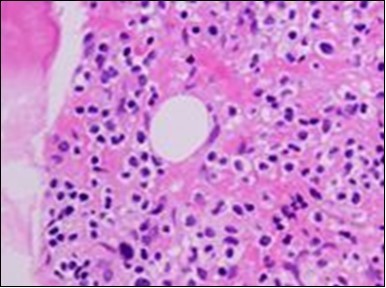

Figure 4.HCL: hairy cells with widely spaced nuclei(20).

The classic hairy cell is medium sized with a magnitude of 10-14µm. The moderately abundant or variable cytoplasm may be transparent or mildly basophilic. The cellular surface with the characteristic serrated perimeter depicts innumerable fragile or stout extensions of cytoplasm ,particularly discernible on the phase contrast and electron microscopy. The cytoplasm may exhibit vacuoles with occasional azurophilic granules4. The nucleus may be elliptical or reniform, folded or indented with a coarse, reticulated or a finely dispersed chromatin and inconspicuous nucleoli along with infrequent mitosis. Bone marrow aspiration or bone marrow trephine biopsy may be inadequate for diagnosis in 30%-50% individuals4. The trephine sections of the bone marrow may depict a characteristic interstitial pattern of leukaemic infiltration. Generally the bone marrow is hyper-cellular, though it may be hypo-cellular in 10-15% individuals4. The leukaemia cell ingress may be diffuse or partial, although diffuse infiltration is frequent. The partial variety of leukaemic dissemination may be ineptly categorized with an indeterminate differentiation from the uninvolved marrow. The malignant insertions may initially emerge as miniature, undefined, cellular loci. The formalin fixed, paraffin embedded sections may elucidate a crystalline zone or a “halo” appearance of the cells with a circumscribed nucleus on account of the plentiful cytoplasm4. The cellular margins may be intertwined. Fixation of bone marrow smears with Zenker’s fixative may demonstrate a retracted cytoplasm of the hairy cells with a consequent disconnected structure. The bone marrow in the absence of a malignant process may be hypo-cellular or hyper-cellular. Reticulin stains may delineate an enhanced accrual of broad, dense reticulum fibres surrounding the aggregates of leukaemia cells with the fibrous circumlocution of individual malignant cell and fibrotic extensions into the abutting, uninvolved bone marrow4.

The leukaemia cells may enunciate a characteristic immune phenotype, crucial for a confirmatory diagnosis. The peripheral blood mononuclear B cell population may display a kappa or lambda light chain restriction. The phenotype of classic hairy cell leukaemia may be delineated by concurrent, immune reactive CD19+ CD20+,CD 11c+, CD25+, CD103+ and CD123+. An intensely immune reactive CD200+ and a non reactive CD27- antigen may be present2, 4. Evaluation of a trephine bone marrow biopsy and bone marrow aspirate may define the degree of tumour infiltration. A dry tap on account of prominent bone marrow fibrosis may be elucidated at preliminary diagnosis. A decline in the normal haematopoiesis may account for a hypo-cellular marrow in 10% instances. Gradation of cellular infiltrating of the leukaemia within the bone marrow may be appropriately investigated with immune –histochemical stains2, 4. Immune staining for CD20+, annexin 1 and VE1 (a BRAF V600E stain] may validate the diagnosis and precisely analyse the extent of malignant bone marrow infiltration[8]. Determination of BRAF V600E mutation may be critical in therapeutically non responsive individuals with applicable standard therapy or in instances of multitudinous reoccurrences[9]. Deploying inhibitors of BRAF V600E gene may be efficacious in patients impervious to approved therapy. The mutation necessitates a comprehensive scrutiny of the implicated individuals with a sensitive molecular assay which may discern up to < 10% of the hairy leukaemia cells appearing in the peripheral blood smears or bone marrow aspirates diluted with peripheral blood or aspirates elucidating a dry tap[2,4]. Allele specific polymerase chain reaction (PCR) or a next generation sequencing may be optimally employed to circumvent false negative outcomes. If the leukaemia cells are sparse or if particularly sensitive & efficacious molecular techniques are not accessible, the application of appropriate immune histochemical stains to the bone marrow biopsy such as a BRAF V600E mutation stain (VE1) may detect the hairy cells and conclusively diagnose the condition[2,4,10]. Figure 1, Figure 2, Figure 3, Figure 4, Figure 5, Figure 6, Figure 7, Figure 8, Figure 9, Figure 10, Figure 11, Figure 12, Figure 13, Figure 14.